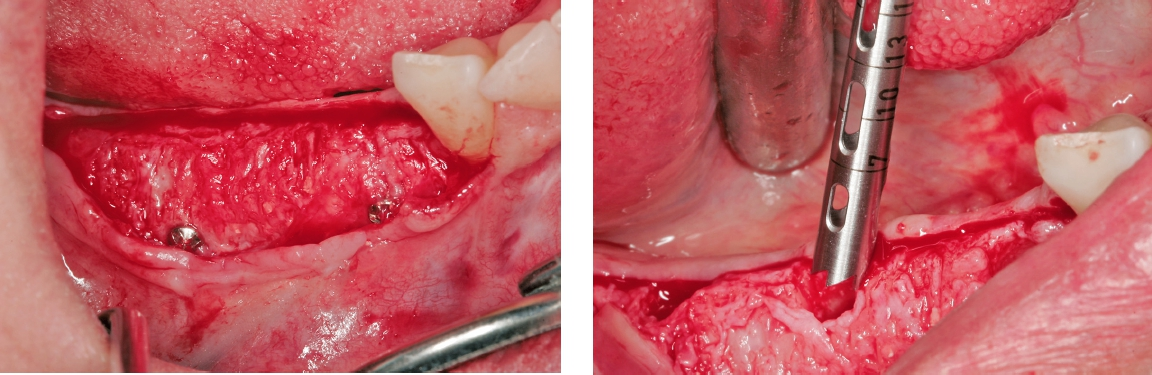

Das GBR-Verfahren wurde unter Lokalanästhesie durchgeführt. Zunächst wurde ein vestibulärer Volllappen mit mesialen Entlastungsinzisionen abgehoben. Das linguale Weichgewebe wurde stumpf, d. h. ohne scharfe Inzision, und unter Schonung der neurovaskulären Gewebe bis hinunter zum Kieferzungenbeinmuskel sorgfältig vom Restknochen gelöst und nach bukkal mobilisiert, um ein adäquates Weichgewebemanagement zu ermöglichen. Um die Blutversorgung zu fördern und die Revaskularisation des Transplantats zu beschleunigen, wurde die Kortikalis an einigen Stellen des Defekts mit einem kleinen Rosenbohrer angefrischt (Abb. 4). Der individuelle allogene Knochenblock wurde exakt in die Defektstelle eingepasst und mit Schrauben (Ø 1,25 mm, Länge 8 mm) im Unterkieferknochen fixiert (Abb. 5).

Der Lappen wurde reponiert und mit nicht resorbierbarem Nahtfaden der Stärke 4.0 adaptiert. Um einen spannungsfreien Wundverschluss zu erreichen, wurde apikal eine laterale Matratzennaht gesetzt. Die Nähte wurden nach 14 Tagen entfernt. Nach sechs Monaten komplikationsfreier Wund- und Einheilung kam die Patientin zur Implantatbehandlung erneut in die Praxis (Abb. 6 und 7). Beim Re-Entry wurden die Befestigungsschrauben entfernt, und es wurde eine Knochenkernbiopsie für die histologische Analyse entnommen (Abb. 8 und 9). Die histologische Untersuchung der mit Hämatoxylin-Eosin eingefärbten Schnittpräparate der Probe zeigte den laufenden Umbauprozess des FDBA-Blocks. Die histologische Aufnahme (Abb. 10) zeigte neu gebildeten Geflechtknochen (WB) in engem Kontakt mit dem Allograftmaterial (*) und umgeben von Bindegewebe (CT) und belegte die durch das Allograftmaterial vermittelte Knochenregeneration. Nach Bestimmung der geeigneten Implantatpositionen wurden in regio 47, 46 und 44 drei Bone Level Implantate Straumann® BLX Roxolid® SLActive ® mit einem Durchmesser von 4,5 mm und einer Länge von 10 mm gesetzt (Abb. 11 bis 14). Die Implantate wurden mit RB Verschlusskappen verschlossen, der Wundverschluss erfolgte mit Nahtmaterial der Stärke 4.0 (Abb. 15 und 16).